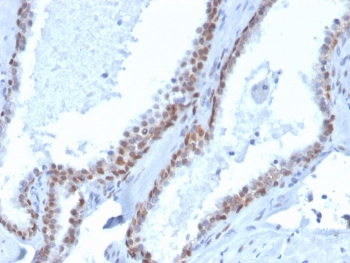

p40 Antibody Biotin Conjugate. Immunohistochemistry analysis of Tumor protein p40 (deltaNp63) in FFPE human prostate tissue using a p40 Antibody Biotin Conjugate (clone rTP40/3690) demonstrates strong HRP-DAB brown nuclear staining in basal epithelial cells lining glandular structures, while luminal secretory cells remain negative. The staining forms a continuous basal layer pattern outlining prostate glands, consistent with the known localization of deltaNp63 in basal cell compartments. The biotin-streptavidin detection system enhances signal intensity, resulting in crisp nuclear staining with clear contrast against surrounding stromal tissue. This pattern supports accurate identification of basal cell populations and epithelial organization within prostate tissue. Heat-induced epitope retrieval was performed by boiling tissue sections in pH 9 10mM Tris with 1mM EDTA for 20 minutes followed by cooling prior to antibody incubation.